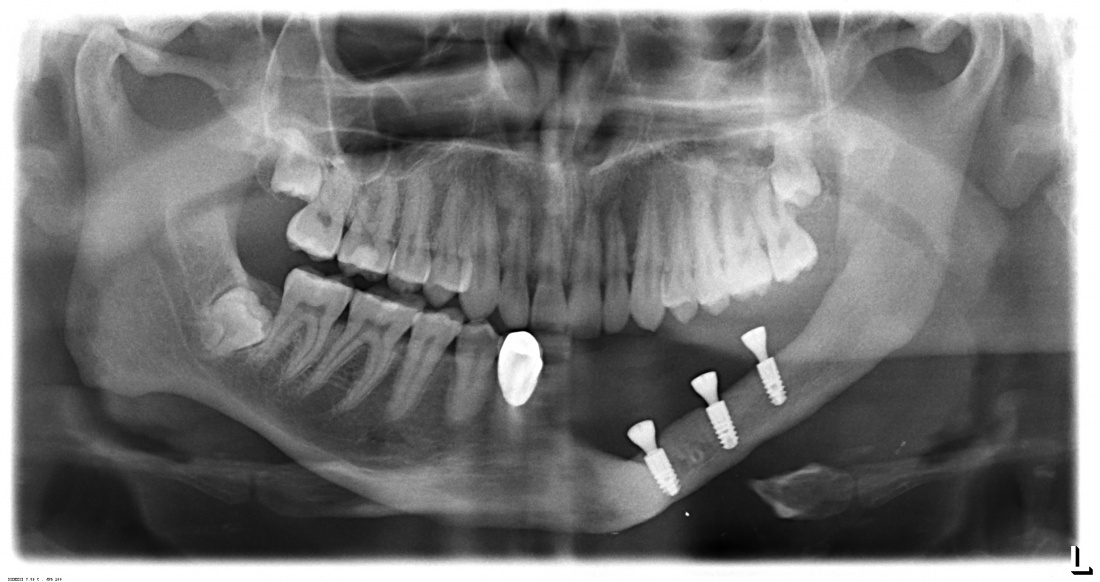

Второй момент, не менее важный — это отсутствие какого-либо усилия при установке имплантатов в подготовленную лунку. Проще говоря, мы вложили имплантаты в лунки с нулевым моментом силы (торком) и без всякого вращения. В итоге получилось это:

При установке имплантата в области верхней челюсти справа выяснилось, что графт, использованный при синуслифтинге, не интегрировался и представлял собой фиброзный конгломерат вперемежку с отдельными гранулами биоматериала. Ежу понятно, что имплантация без повторного синуслифтинга здесь невозможна, что мы и делаем одновременно с установкой имплантата.